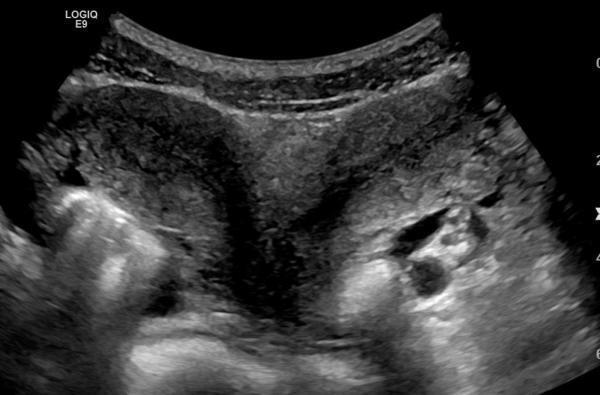

(Bild: Symbolbild/Wikimedia Commons/Mme Mim/CC BY-SA 4.0)